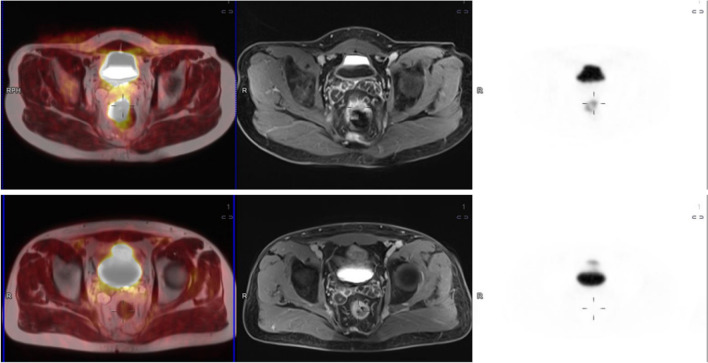

PET-MRI data sets were reviewed on a commercially available workstation (Fig. 1) (Syngo.Via, Siemens Healthcare, Erlangen, Germany) by a radiologist and a nuclear medicine physician, both with more than 10-years’ experience in MRI and PET/CT, respectively. For all tumors, the maximum SUV was analyzed in the PET dataset of the rectum plotting an isocontour volume of interest (VOI) around the tumor (SUVmax threshold 40%) by the nuclear medicine physician. ADC maps were automatically generated by the implemented software. After a qualitative evaluation of the ADC map, two regions of interest (ROI) in two different slices were manually drawn on this map in the area with the minimal signal intensity inside the tumor. In all lesions, two minimal ADC values (ADCmin) were registered. The response was assessed using the Mandard system’s mrTRG classification in MRI sequences (mrTRG) and in PET/MRI (petmriTRG), where TRG 1 indicates only low signal fibrosis without tumor signal, TRG 2 signifies more than 75% fibrosis with minimal tumor signal intensity, TRG 3 represents a balance of 50% tumor and fibrosis, TRG 4 suggests less than 25% fibrosis with predominant tumor signal, and TRG 5 indicates no fibrosis. The radiologist underwent specialized training in primary tumor assessment using TRG as part of a program run by leading experts in the field, which included reporting post-neoadjuvant treatment. The radiologists reviewed the images and were in consensus, while information on the histopathology results and patient outcomes was not provided to them.

Fig. 1.

18F-FDG PET/MRI sequences before and after neoadjuvant radiochemotherapy